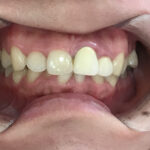

術後の経過・現在のご様子

きれいに整った歯並びでしっかり噛めるようになり、笑顔も素敵になりました。

患者様にも「口元を気にせず過ごせるようになった」と大変お喜びいただきました。

現在は歯並びの後戻りを予防するための「保定装置」をご使用いただき、経過を拝見しています。